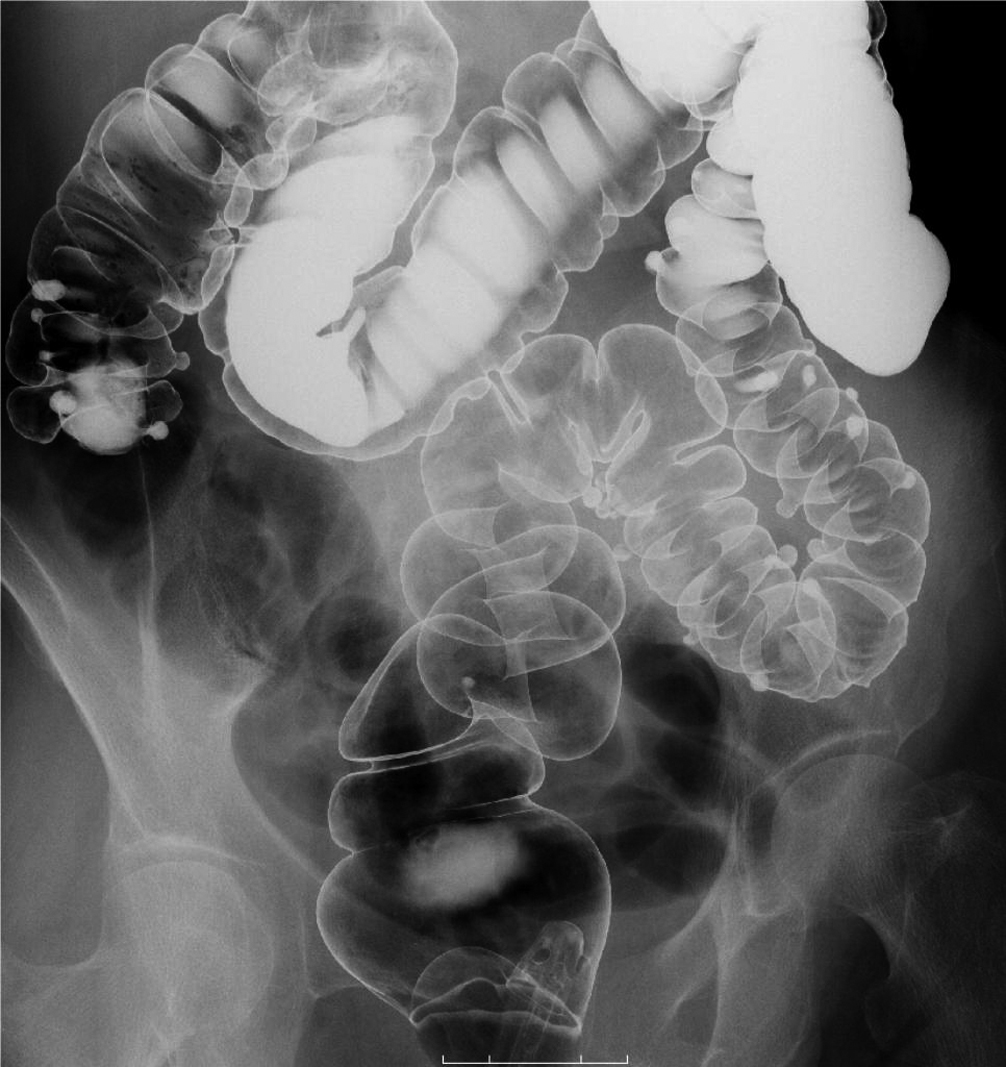

- 消化管造影検査(食道・胃・小腸・大腸検査) 造影剤(バリウム)を使って消化管を観察する検査です。

Q2) どうして胃や大腸の検査の時、回転したり体を動かしたりするのですか?

|

![]() |

A2) 胃や腸の壁の内側にバリウムを付着させて観察する検査なのでムラなく壁全体にバリウムを着けるためです。 |